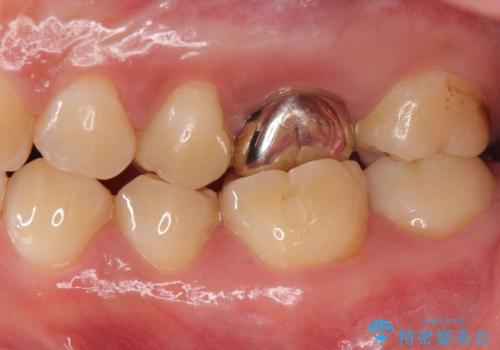

不適合な被せ物 ジルコニアクラウンでの再治療

- 検査の結果被せ物の不適合が見つかった患者様です。

ご妊娠中で安定期に治療を終わらせたいとのご希望があったため、大掛かりな外科処置は避けた治療方針で進めていきます。

本来は歯茎をしっかりと下げる外科処置が適応となるケースでしたが、ご希望がなかったため最小限の侵襲に抑えて治療を行いました。